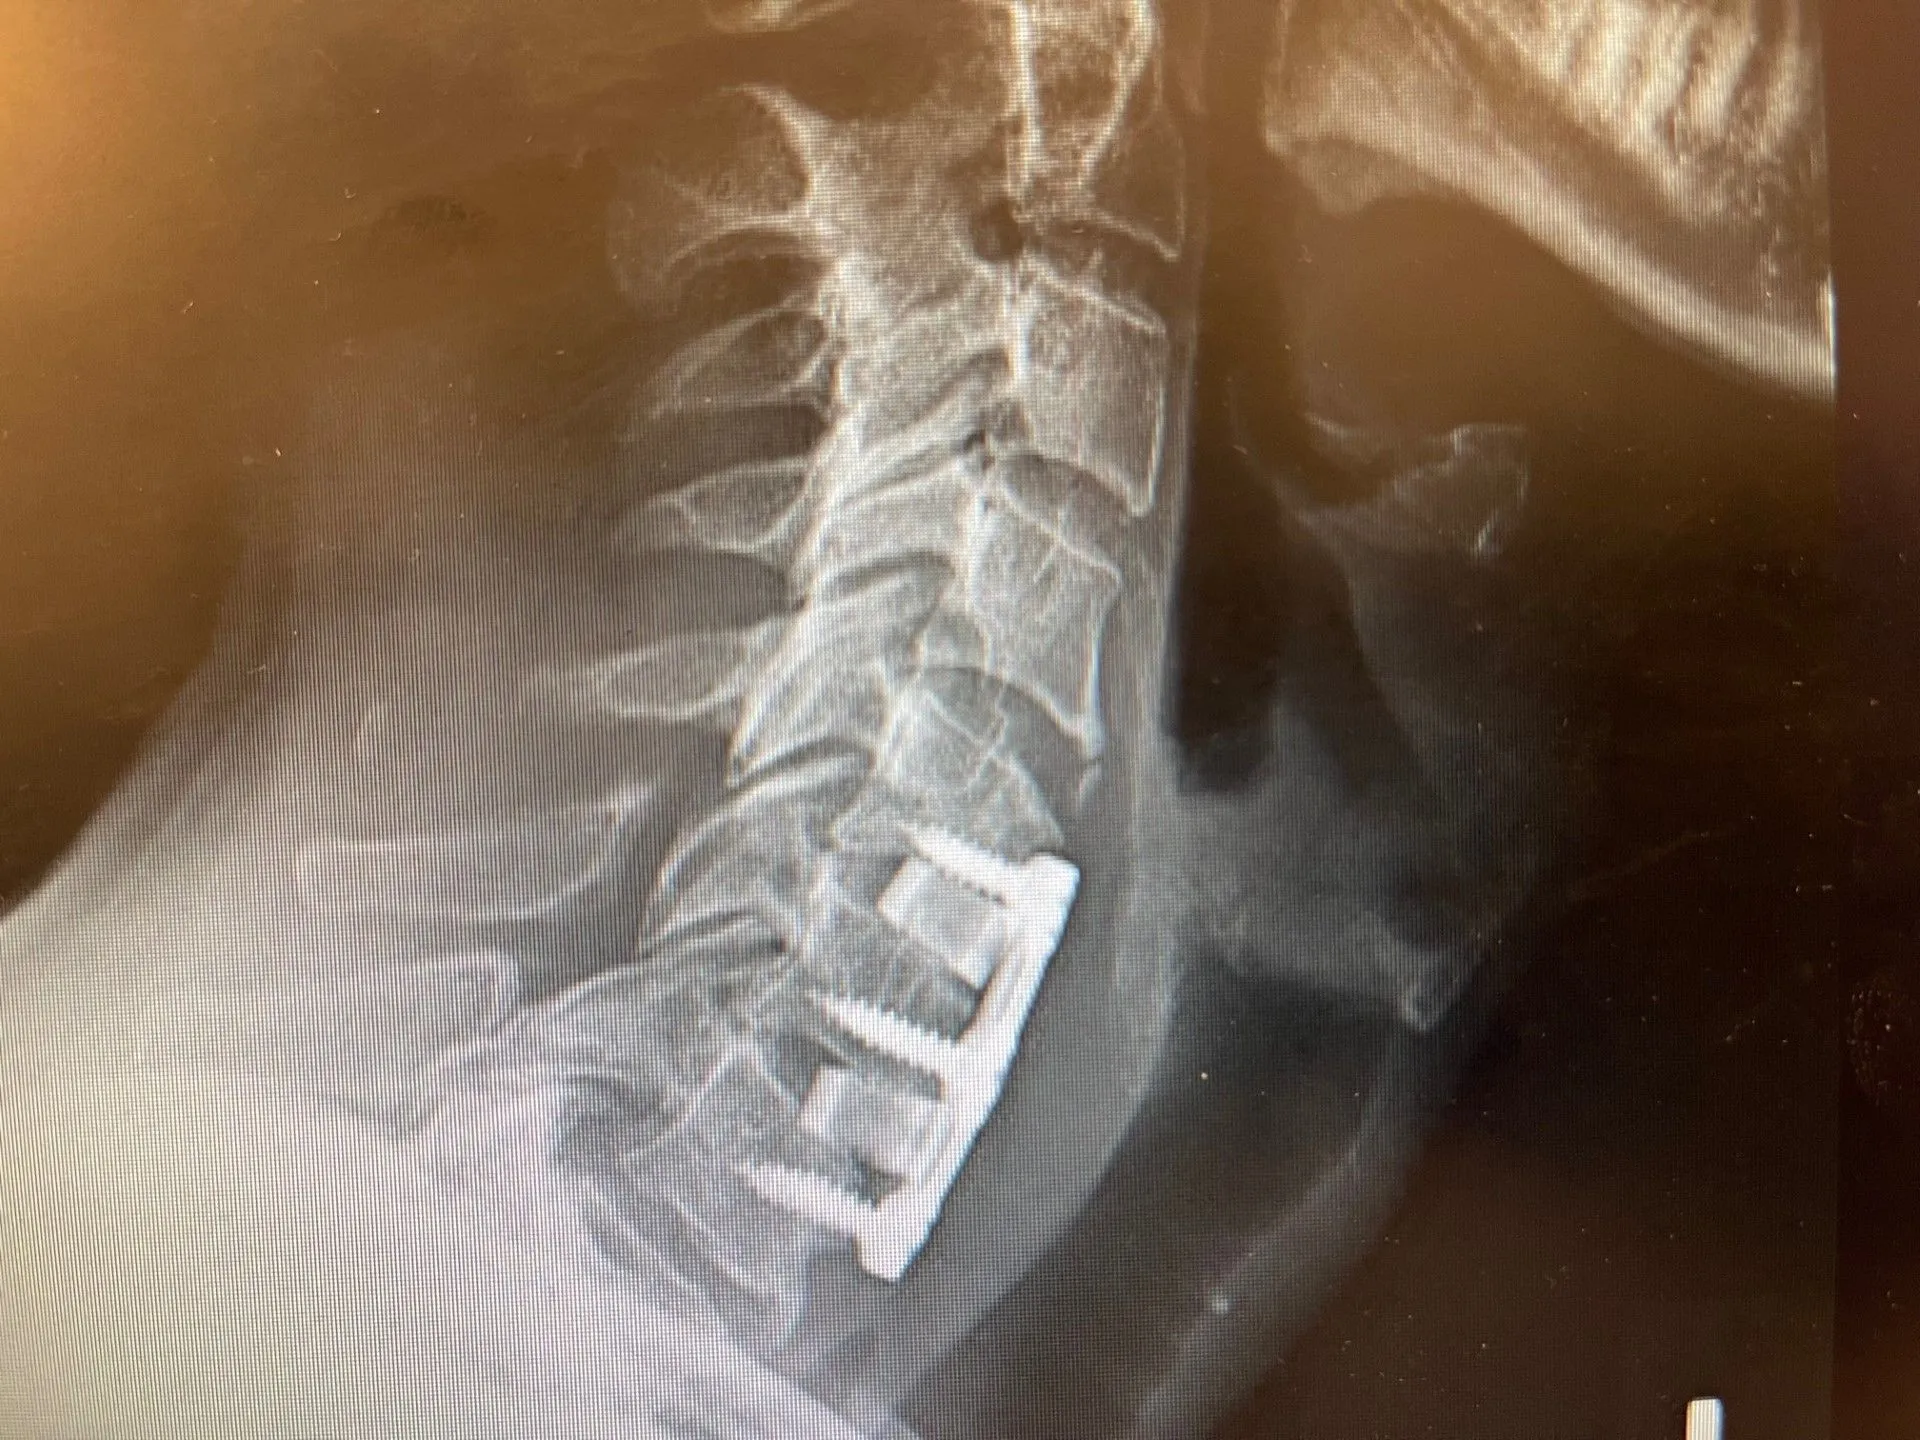

CT Myelography

In some cases, particularly when MRI is not feasible or when bony detail is required, computed tomography (CT) myelography may be used. This involves injecting contrast dye into the spinal canal and then performing CT imaging to visualize the nerve roots and any compressive pathology. A 2024 update on cervical radiculopathy imaging published in the Journal of the American College of Radiology confirmed that CT with contrast myelography remains a high-value imaging tool when MRI results are inconclusive. 3

A CT scan of 3 level cervical fusion depicting complications.